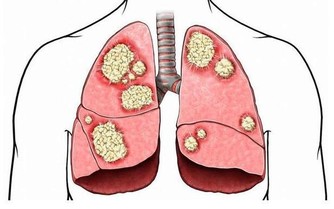

*****3、免疫功能下降*****

一般我們人體的各項器官在晚上都是要進行休息的,但是有很多人就會選擇在晚上玩手機,從而就會促使大腦或者一些器官仍在繼續工作,處在興奮狀態,長期下去就會擾亂體內的內分泌,從而使得體內的免疫系統也逐漸下降,容易被疾病纏身。